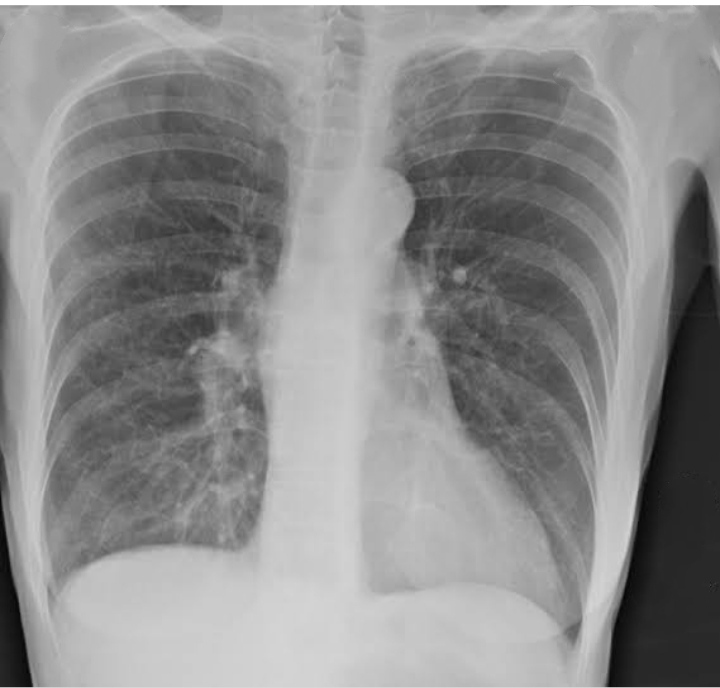

Diagnosis :

History collection

Physical examination

Chest x ray

CT scan

Pulmonary function test

ABG analysis